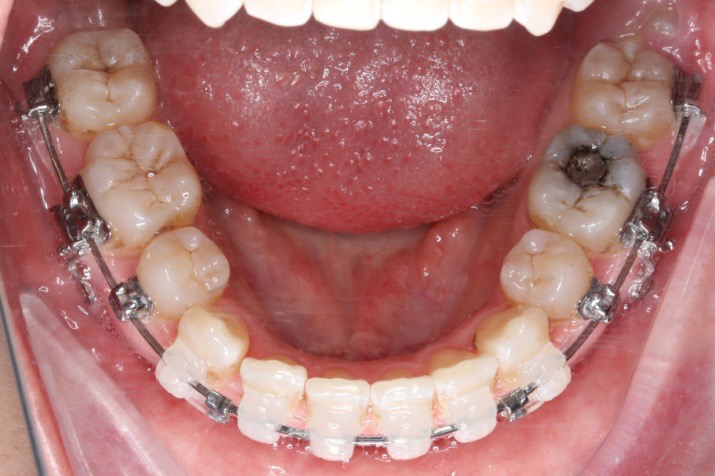

2017.05.26  磨牙近中倾斜,下颌36、46加power arm

下颌磨牙通过powerarm直立效果明显,下颌整平效果明显

2017.04.28

2017.05.26

2017.10.07